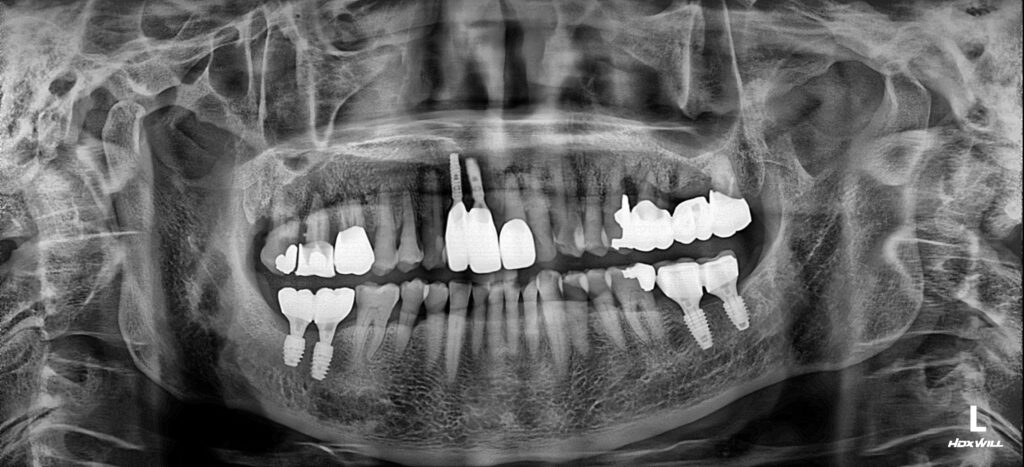

앞니 2개의 임플란트와 잇몸라인에 맞는 보철물을 제작한 모습입니다. 앞니 임플란트 식립의 경우상대적으로 어금니 부위보다 치조골이 얇고 치주질환까지 동반되어 매우 고난이도의 수술이었습니다.

뼈 이식과 치조골의 폭과 높이에 맞는 인공치근(픽스쳐)의 식립으로 성공적으로 마무리해드릴 수 있었습니다. 환자분께서도 걱정이 많으셨는데 영도임플란트 서울화이트S치과의 섬세한 치료덕분에 자신감을 되찾으셨다고 말씀주셨어요:)